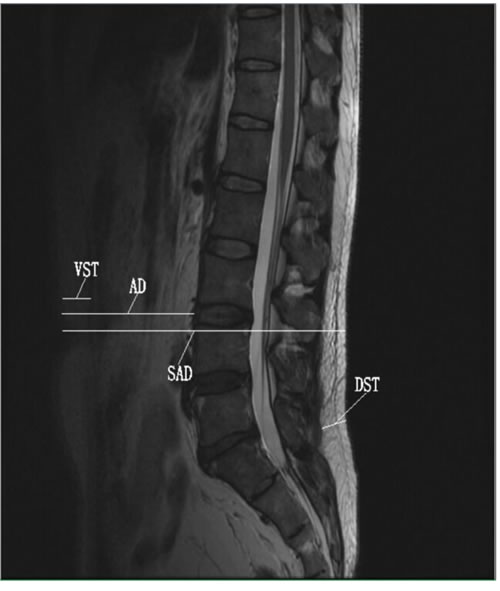

Figure 1: T2-weighted midsagittal plane images of the lumbar spine showing the adiposity diameters measured. Abbreviations: VST, ventral subcutaneous thickness; AD, abdominal diameter; SAD, sagittal diameter; DST, dorsal subcutaneous thickness.

Anthropometric and adiposity measures